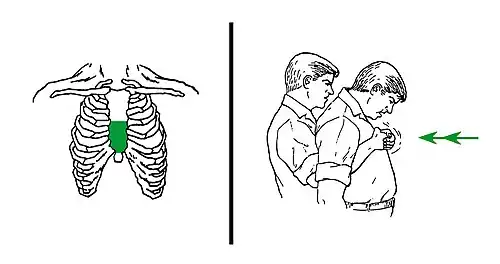

| A demonstration of abdominal thrusts on a person showing signs of choking | |

Abdominal thrusts (Heimlich maneuver)

Abdominal thrusts[37] are performed with the rescuer embracing the belly of the choking victim from behind. Then, the rescuer closes their own dominant hand, grasps it with the other hand, and presses forcefully with them on the area located between the chest and the belly button of the victim, in a direction of in-and-up. This method tries to create enough pressure upwards to expel the object that obstructs the airway. The strength is not focused directly against the ribs, to avoid breaking them. If the first thrust does not solve the choking, it can be repeated several times.

The use of abdominal thrusts is not recommended for infants under 1 year of age due to risk of causing injury, so there are adaptations for babies (see more details further below), but a child that is too big for the babies' adaptations would require normal abdominal thrusts (according to the size of the body). Besides, abdominal thrusts should not be used when the victim's abdomen presents problems to receive them, such as pregnancy or excessive size; in these cases, chest thrusts are advised (see more details further below).

Although it is a well known method for choking intervention, the Heimlich Maneuver is backed by limited evidence and unclear guidelines. The use of the maneuver has saved many lives but can produce deleterious consequences if not performed correctly. This includes rib fracture, perforation of the jejunum, diaphragmatic herniation, among others.[38]

Chest thrusts

When abdominal thrusts cannot be performed on the victim (serious injuries, pregnancy, or belly size that is too large for the rescuer to effectively perform abdominal thrust technique), chest thrusts are advised instead.[39]

Chest thrusts are performed with the rescuer embracing the chest of the choking victim from behind. Then, the rescuer closes the own dominant hand and grasps it with the other hand. This can produce several kinds of fists, but any of them can be valid if it can be placed on the victim's chest without sinking a knuckle too painfully. Keeping the fist with both hands, the rescuer uses it to press forcefully inwards on the lower half of the chest bone (sternum). The pressure is not focused on the very endpoint (named xiphoid process) to avoid breaking it. When the victim is a woman, the zone of the pressure of the chest thrusts would normally be above the level of the breasts. If the first thrust does not solve the choking, it can be repeated several times.